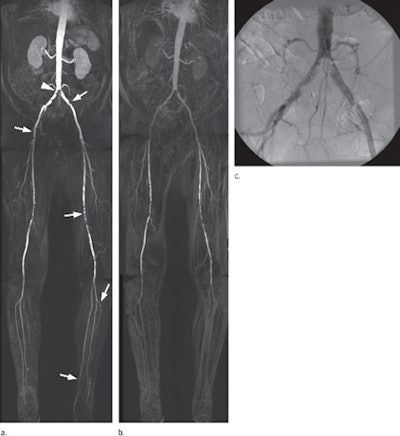

MR images are of a 72-year-old man showing moderate claudication in right and left thigh and calf after a dose of 0.1 mmol/kg of gadobenate dimeglumine (a) and gadopentetate dimeglumine (b). Gadobenate dimeglumine results in better visualization of peripheral arterial vasculature and better depiction of vascular disease. There is better delineation of plaque formation in aortic bifurcation (arrowhead, a) extending to both iliac arteries, and clearer depiction of extent of stenosis (arrow) in left common iliac artery is achieved, relative to corresponding DSA image (c). Better enhancement of thigh station with gadobenate dimeglumine allows exclusion of significant stenosis (arrow) in right common femoral artery, while multiple stenoses (arrows) in left superficial femoral artery are better seen. Images courtesy of Radiology.